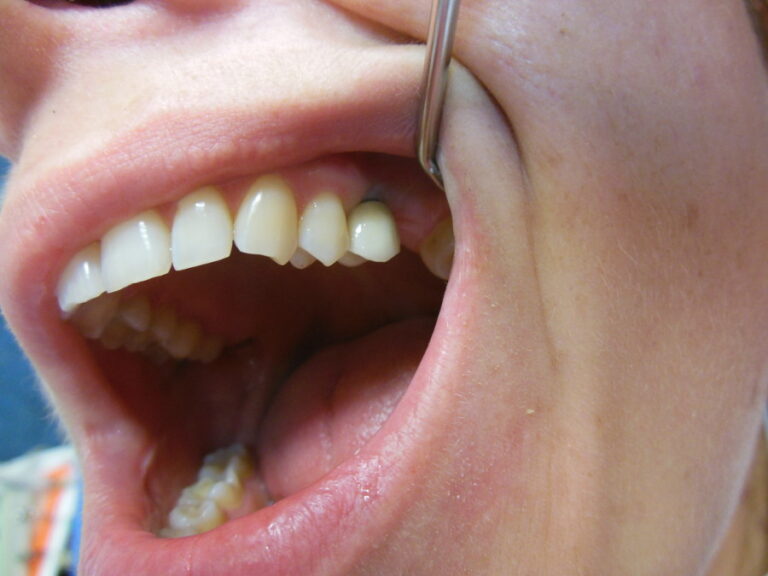

Ortodoncja CBCT

Leczenie chirurgiczno-ortodontyczne wad zębowych z zastosowaniem tomografii spiralnej CBCT w naszej klinice.